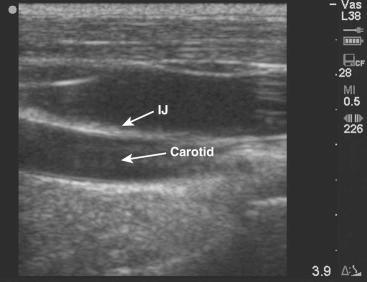

Once a site has been chosen, usually the internal jugular or femoral, it should be evaluated with ultrasound to identify the artery and the vein ( Figure 69-1-3 ). When compared with their accompanying veins, arteries appear thick walled, more circular, and pulsatile on ultrasound. Arteries do not compress with light pressure. Veins are more irregular in shape, sometimes appearing triangular rather than round, and compress with light pressure. Use of color Doppler can also aid in identification.

F igure 69-1-3, Transverse anatomy of the vessels of the neck.

It is often easiest to begin with the probe in a transverse orientation. In this view, the vessels appear in cross section as round or oval structures (see Figure 69-1-3 ). The depth of the target vessel and its relationship to surrounding structures can be determined. The vein should then be centered on the screen. This allows an external landmark, the center of the transducer, to be established. Pressure over this area with a blunt object, such as a fingertip, can confirm the correct location. The needle should then be inserted at a 45-degree angle to the skin at a distance from the probe equal to the depth of the target vessel ( Figure 69-1-4 ). Immediately after entering the skin, the needle tip should be identified on the screen. It will appear as a hyperechoic (white) object within subcutaneous tissue. The needle tip should be followed with the transducer as it advances toward the vein. As the needle tip reaches the vein, the wall of the vessel will be seen to deform. A flash of blood in the syringe confirms that the needle has entered the vein ( Figure 69-1-5 ).